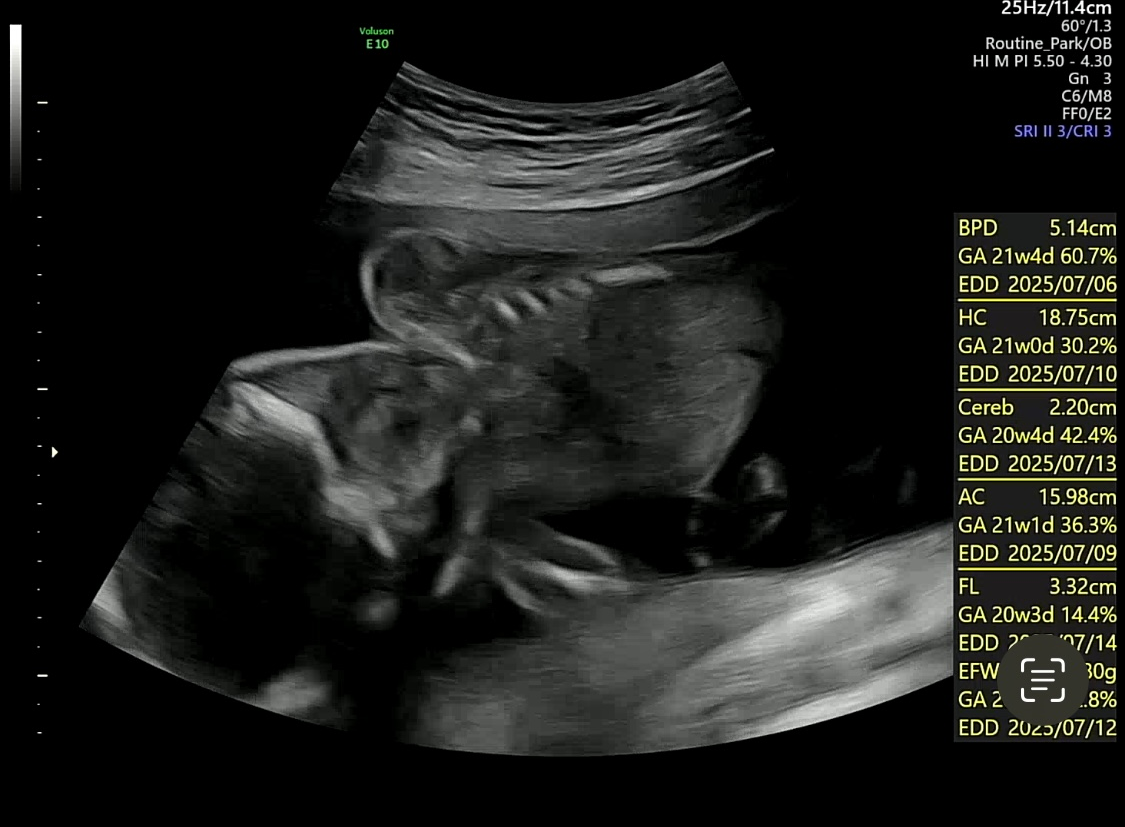

머리둘레, 뇌 크기, 눈의 수정체

심장 좌심 우심 방네개와 대동맥

폐혈관, 위, 콩팥, 방광, 척추, 허벅지뼈, 생식기, 얼굴, 태반 혈류 등등

하나하나 사진으로 찍어서 설명해주시고

다행히 모든 검사결과 이상없이 주수대로 잘 자라고 있다고 한다 :)

주수대로 잘 크고 있다고 아주 문제없다면서

손가락 발가락 한번 더 보여주시고

머리 사이즈 등 사이즈도 한번 더 봐주셨다.